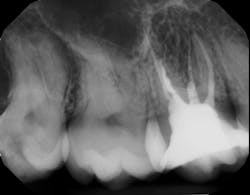

Saving compromised multirooted teeth with root amputation can often be successful, but the technique is sensitive and complex. Proper case selection is essential, and considerations include the following:

There is sufficient bone support around the remaining roots (at least 50% or more is needed) along with sufficient coronal tooth structure (figure 3).How does root amputation compare with other surgical procedures?